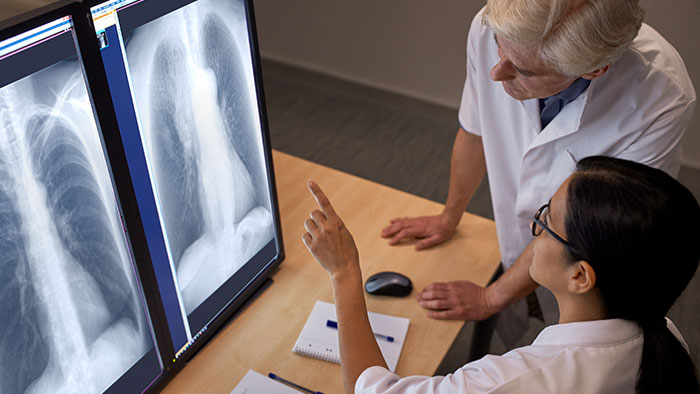

Ver SkyFlow Plus en funcionamiento

Compárelo con un procesador de imágenes convencional para ver los beneficios usted mismo.